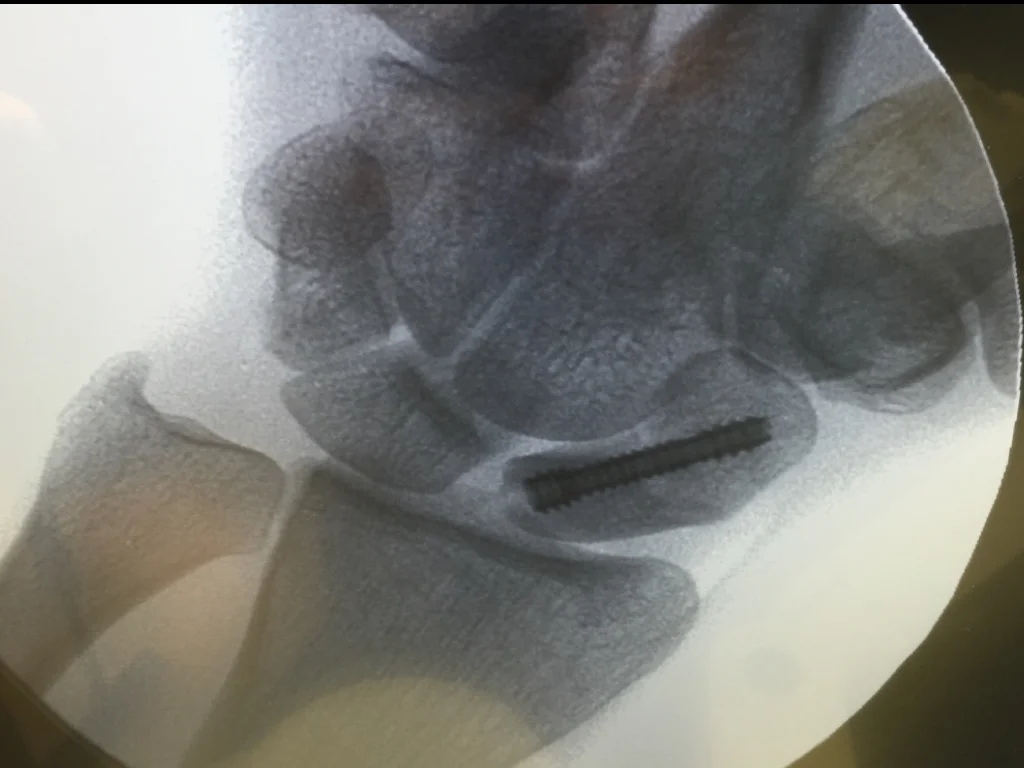

Comprehensive Orthopaedic Hand Surgery practice in Chicago's North Shore.